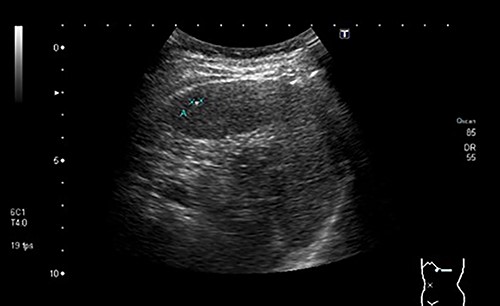

During a screening imaging examination of her liver disease, a lesion suspected of malignancy was detected. The ultrasound disclosed a hypoechoic nodule, vaguely heterogeneous, located in segment VII, subcapsular, and with ~22 mm in diameter (Fig. 1). Liver blood tests and serum alpha-fetoprotein level were normal. For better characterization, a CT scan was performed. The CT showed, in addition to signs of chronic liver disease, the presence of a solid subcapsular nodule of segment VII, measuring 23 mm, with hypervascular behavior in the arterial phase (Fig. 2) and washout in late venous phase (Fig. 3).

CT scan showing the same mass as shown in Fig. 2 but with washout in the portal venous phase.